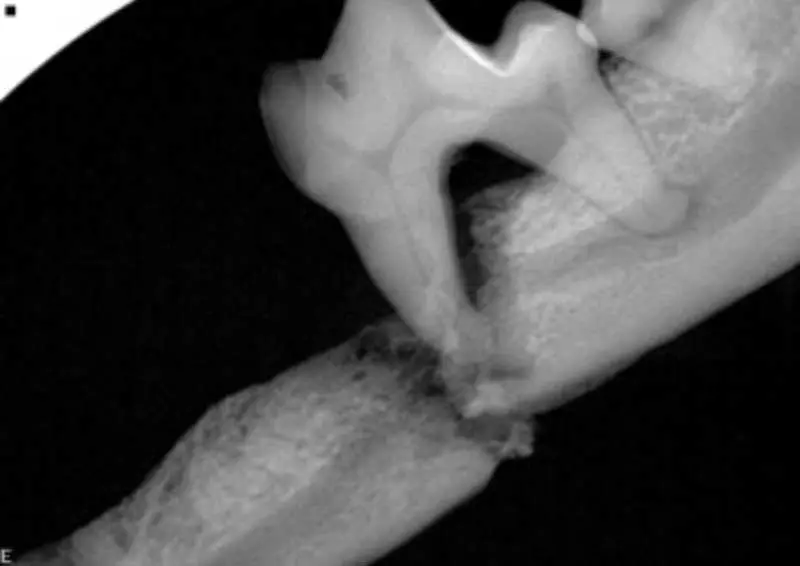

Stage 4 – advanced periodontitis

In the advanced stage of periodontal disease, bone loss exceeds 50%. At this point, tooth loss is common due to the loss of the alveolar bone and periodontal ligament. The patient may experience significant pain and discomfort (Figure 6).

Symptoms may include:

- Pain.

- Extensive tooth mobility (single-rooted teeth and multi-rooted teeth).

- Tooth loss.

- Severe gum recession and inflammation.

- Large pockets around the teeth.

- Difficulty eating or reluctance to chew.

- Halitosis.

- Noticeable discharge or pus around the gums.

- Becoming head-shy.

Loss of teeth and mandibular fractures. In severe cases, if left over time, the weakened bone structure may make the mandible more susceptible to pathological fractures (Figure 9).